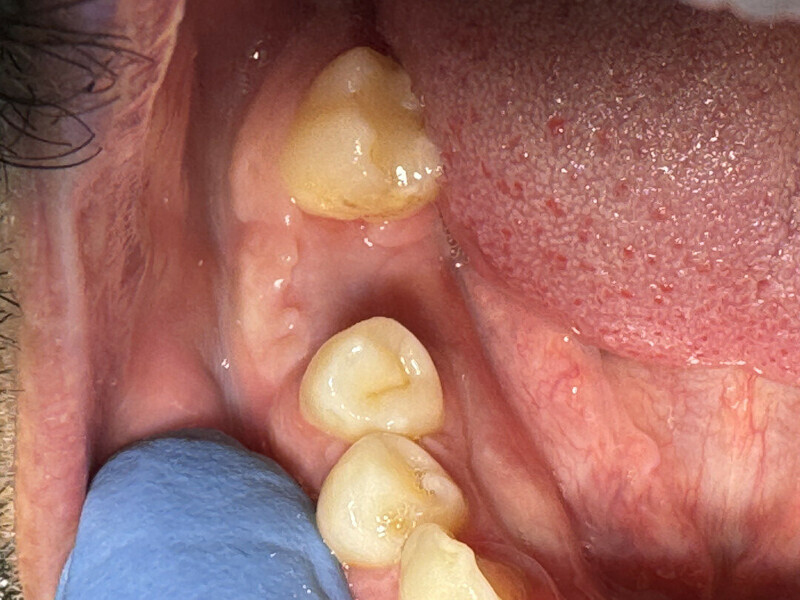

C’est sa structure et composition spécifique qui va permettre la non-compétition cellulaire et par la même la constitution de l’os sous la membrane. Les cellules épithéliales vont, quant à elles, se développer en tapissant la surface lisse de cette membrane (Figs. 2 et 3).

On pourra remarquer que la membrane a été volontairement laissée exposée, afin de ne pas lever de lambeau vestibulaire ou lingual. Grâce à ceci, nous avons pu conserver la totalité de cette muqueuse attachée, ce qui nous permettra d’obtenir un résultat esthétique bien meilleur lors de la reconstruction prothétique, qu’elle soit traditionnelle (bridge ou prothèse amovible) ou sur implants, en permettant d’avoir un profil d’émergence le plus proche possible du naturel (Figs. 4–8).